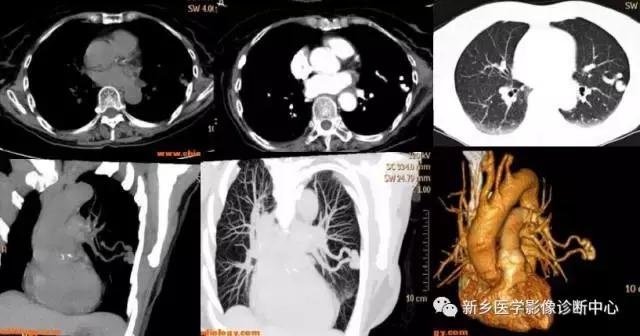

错构瘤

好发于40Y,下肺单发,无明显临床症状。圆形或分叶状,界清,一般密度均匀,少数有爆米花样,点状,环状钙化,内可有脂肪密度。

肺内血肿

有外伤史,胸痛,痰中带血或咯血。早期多为大片实变影,边缘模糊,2周后可出现类圆形密度均匀,边界清楚的球形肿块影。

下图为:车祸2小时血肿,治疗1周血肿,及治疗2周后血肿

肺腺瘤

好发于女性,30-50Y左右,右上叶,中叶,左肺舌叶多见,可有阻塞性肺炎或肺不张,反复咯血。类圆形肿块,密度均匀,界清,光滑锐利,无毛刺及钙化,增强常不强化。

肺硬化性血管瘤

边界光滑,显著强化,周围肺野晕征 。

右上肺海绵状血管瘤,平扫点状钙化灶。